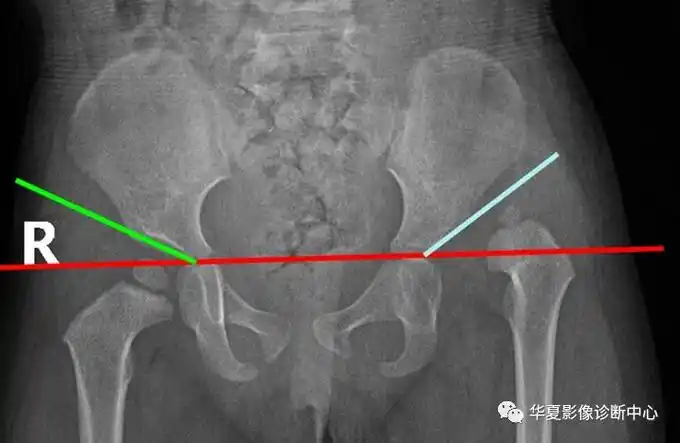

图12 夏普角在骨盆正位片上,双侧泪滴下缘连线与泪滴下缘至髋臼上缘

30°,1岁以后不应超过25°,2岁20°,成人10°,如角度增大表示髋臼变浅